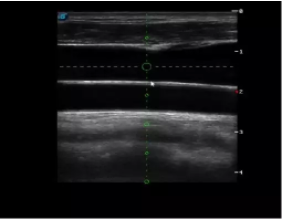

4  置管專用探頭

實(shí)時觀察穿刺針進(jìn)入血管的全過程,方便操作及較短的穿刺路徑,智能進(jìn)針尺寸提示,讓置管工作更加輕松,高效。

不同進(jìn)針路徑